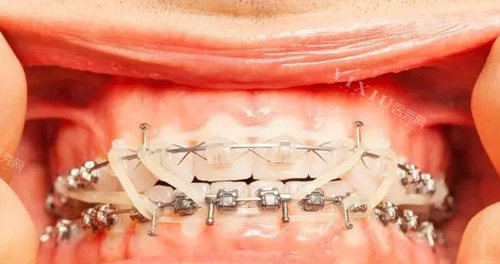

二、成人金属/自锁矫正价格

金属牙套以其经济实惠和稳定的矫正结果,受到许多成人的青睐。

成人传统金属托槽矫正:价格区间大约在7200元起,性价比高,适合大部分需要矫正的成人。

国产自锁金属托槽矫正:价格通常在8500元起,相比传统金属托槽,自锁牙套具有更高的舒适度和矫正效率。

进口金属自锁托槽矫正:价格相对较高,如美国3M金属自锁托槽矫正价格可能在17500元起,而德国非凡自锁金属矫正价格则在16000-23000元起。